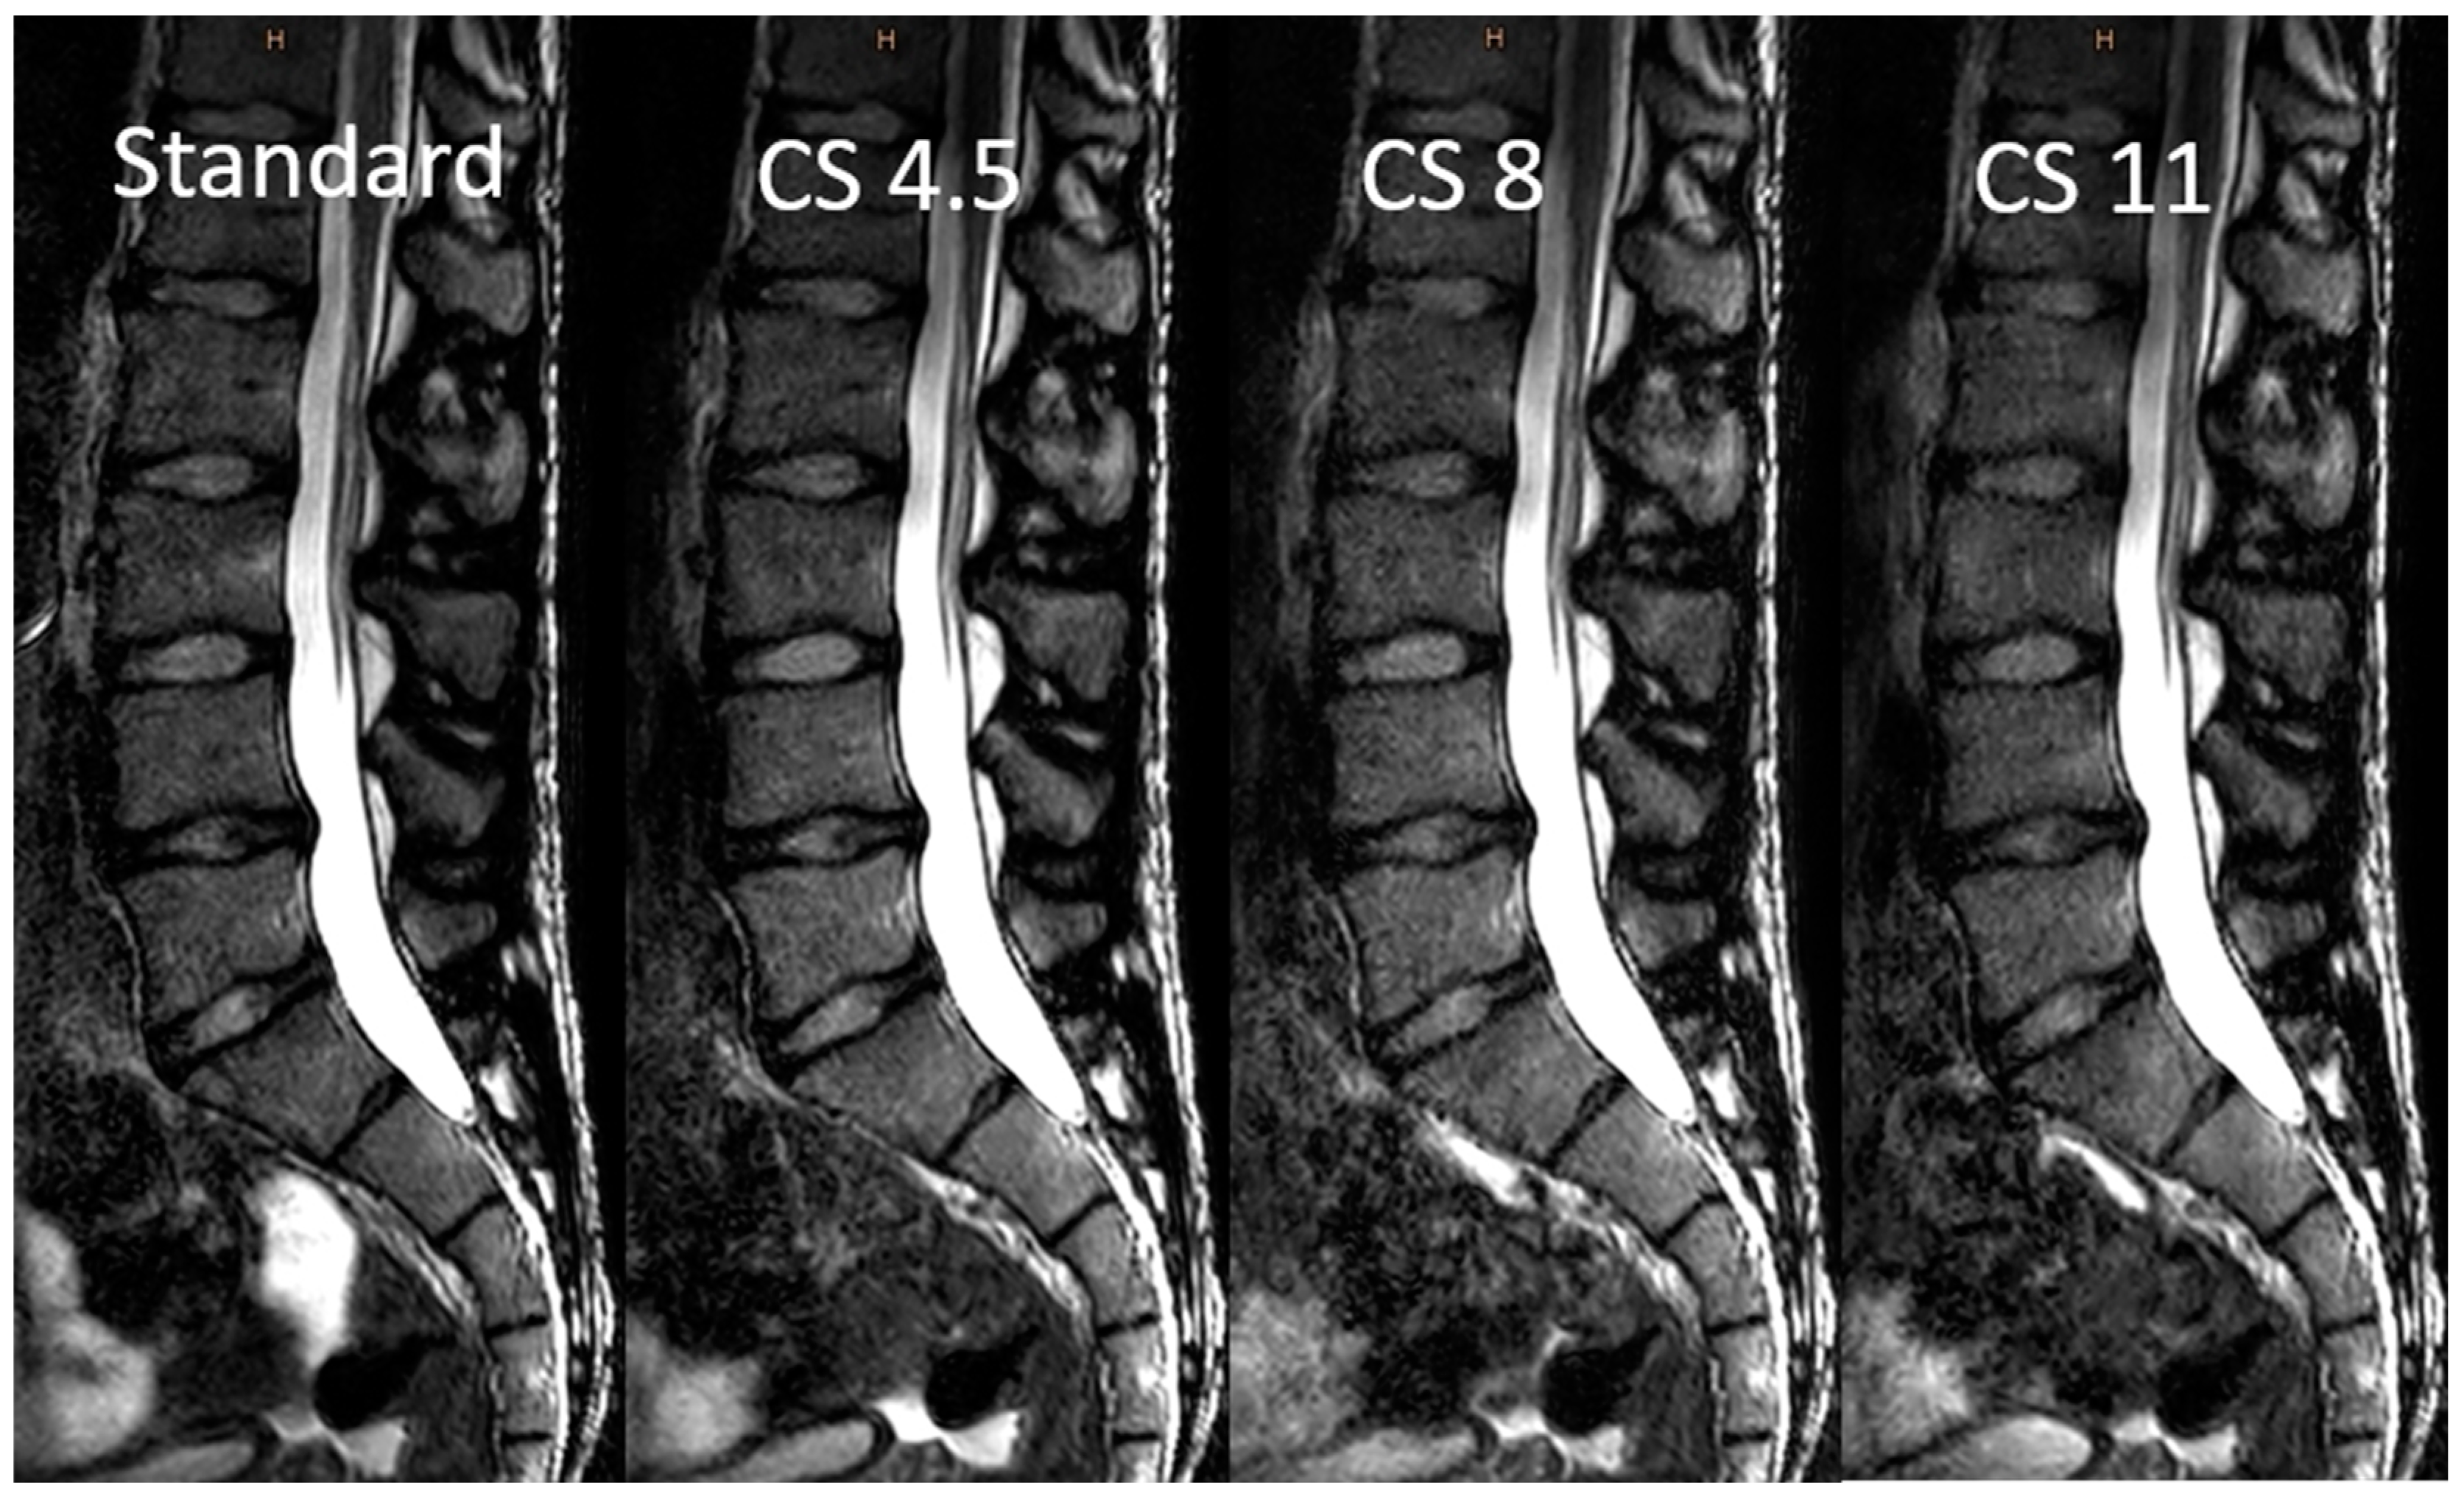

3.2. Image Analysis

3.3. Objective Image Analysis

3.4. Subjective Image Analysis